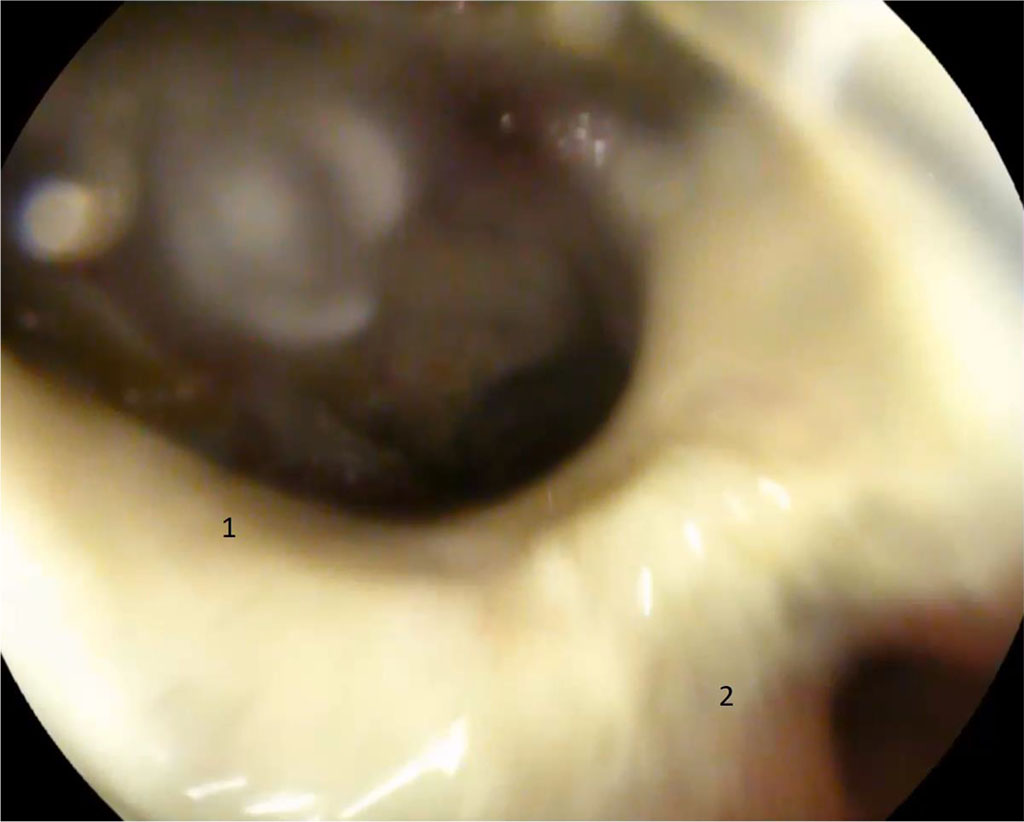

The postoperative period was smooth, however, on the day 4, epigastric discomfort appeared and the temperature increased to 38°C. It should be noted that in patients with severe obesity, the classic clinical picture of peritonitis is not seen and, as a rule, there is no inflammatory reaction in the peripheral blood. EGD revealed a defect of 12 mm in diameter with infiltration at the edges in the prepyloric region. Fig. 1

Figure 1. 4 days after surgery. 1 — gastric fistula along the suture line with an orifice into the abdominal abscess; 2 — pyloric part, orifice into the duodenum (explanations in the text)